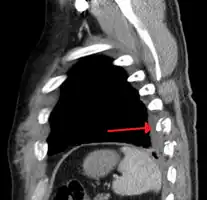

Two broken ribs as seen on parasagittal CT

Plain X-rays often pick up displaced fractures but often miss undisplaced fractures.[13] CT scanning is generally able to pick up both types of fractures.[13]